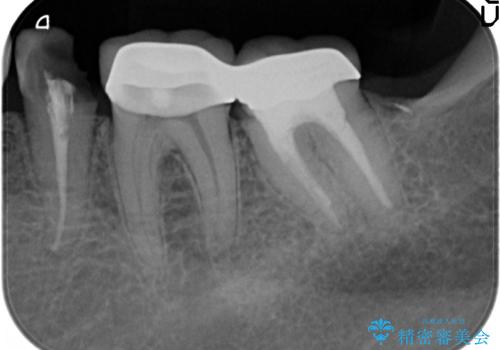

- 左下の歯が虫歯により崩壊し、歯ぐきからの出血も毎回歯ブラシを行う際に出ることから治療を求めて来院されました。

現在装着されているクラウンを除去したところ、クラウンマージンが歯肉縁下となり歯ぐきの炎症が認められたため再度オールセラミッククラウンを製作する前に歯周外科手術を行い歯ぐきの状態を改善しました。